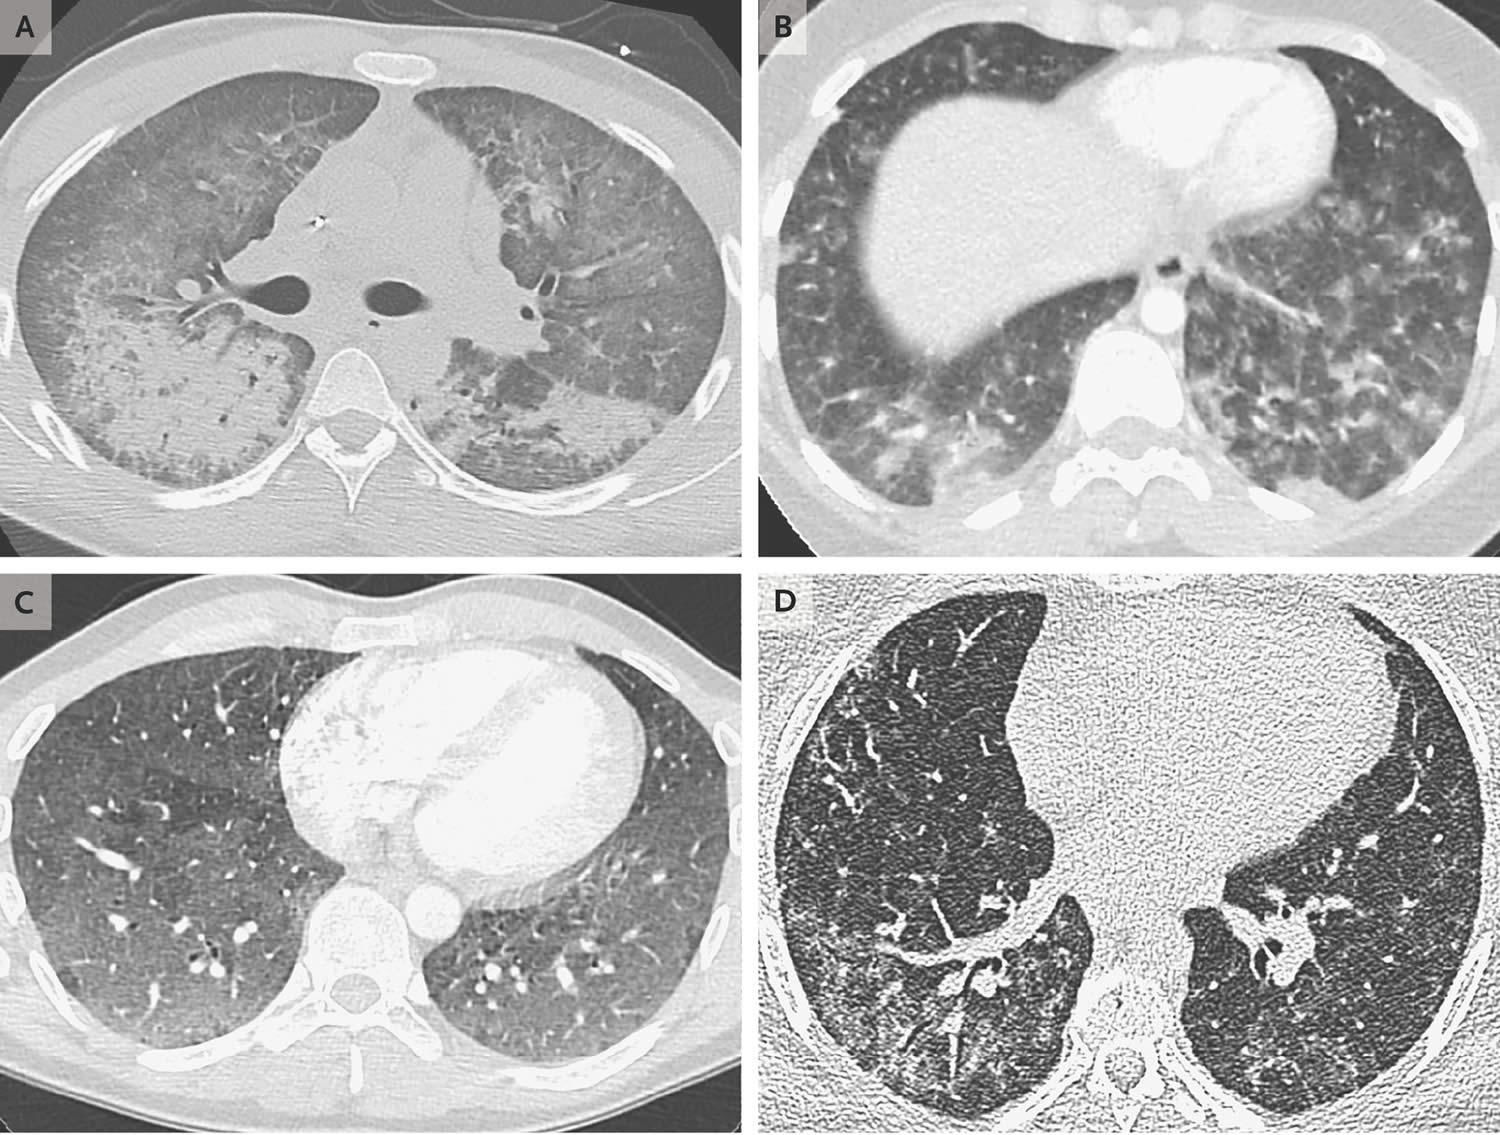

EVALI 3 shocking images reveal the damage vaping can do to teen lungs What Does Evali Feel Like The signs of vaping related lung injury can be vague. Evali can cause symptoms that resemble those of pneumonia or the flu, the cdc warns, including the. “they may not have a. The following can happen suddenly or get worse. What are the symptoms of evali specifically? Learn about symptoms and treatment. What are the signs and symptoms of evali?. What Does Evali Feel Like.